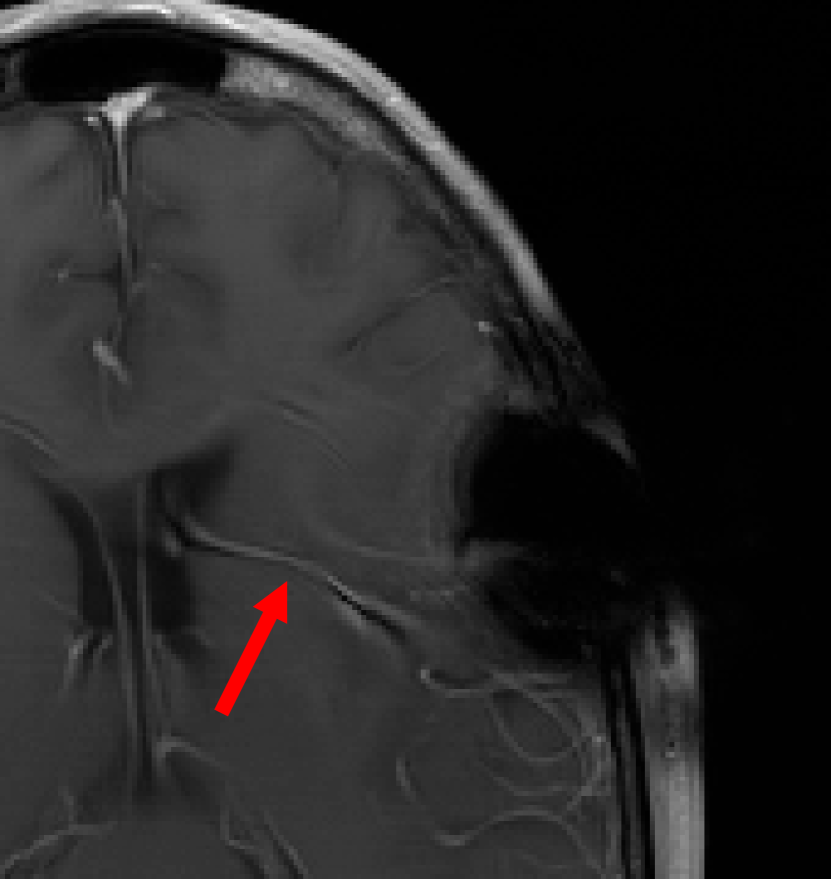

This result implies that random noise can also produce undesirable effects. In Fig. 3 we show several examples of this effect. For the first DL method, mean zero Gaussian noise causes the NN reconstruction map to hallucinate, by artificially removing an image feature (indicated by the red arrow). In the second case, certain image independent, small mean Gaussian noise causes severe instabilities in the recovered image. Notice that the noise causes the second DL method to exhibit completely nonphysical artefacts, which could be easily identified by a practitioner as a failure mode. Yet for the first method it creates seemingly realistic artefacts (hallucinations). Such pernicious artefacts may be impossible to detect.

A.3 Fig. 3

In the four leftmost images, we consider the DeepMRI-Net from [66]. This NN is composed of a cascade of U-Nets and data consistency layers. It has been trained on cardiac images, such as the one shown in the figure. The sampling operator is a subsampled two-dimensional Fourier transform, whose sampling pattern is shown in Fig. 7. The noise vector used in the experiment was created as , where is a zero-mean complex-valued Gaussian noise vector. Since the mean of a Gaussian random variable is unchanged by a linear transformation, the noise vector still has zero-mean.

The four rightmost images are from [7]. Code is available at https://github.com/vegarant/am_AI_hallucinating. Here we consider the AUTOMAP network from [82]. This NN was trained by the authors of [82] on brain images from the MGH–USC dataset [27]. It was trained using Fourier sampling with 60% subsampling. In [7], the perturbations

Here , and , are zero-mean Gaussian vectors. The vectors , , are worst-case noise vectors computed for an image that differs from the image used in the experiment. This makes the mean of the Gaussian noise vector image independent. The image used to compute the worst-case perturbations is shown in Fig. 6.